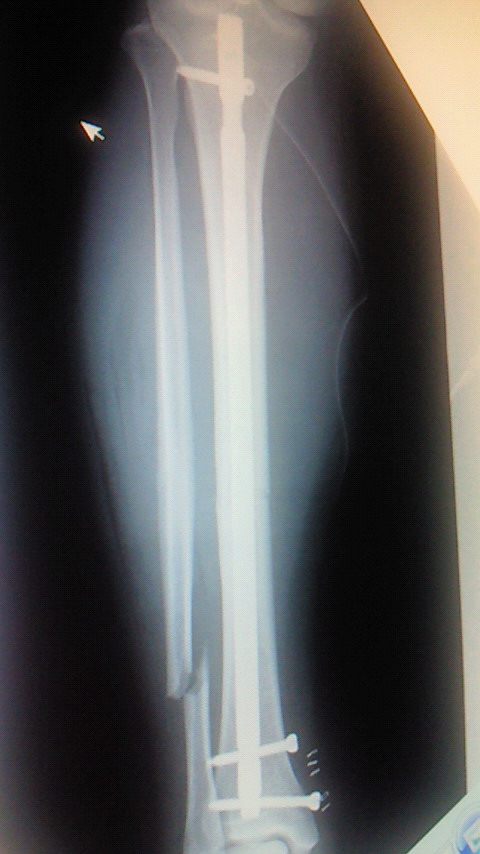

左が術前で右が術後です。(;^_^A

先生にお願いしましてレントゲンをゲットしました!(o^o^o)

右が術前で左が術後です。(@_@;)

腓骨(細い骨)は折れたままです。